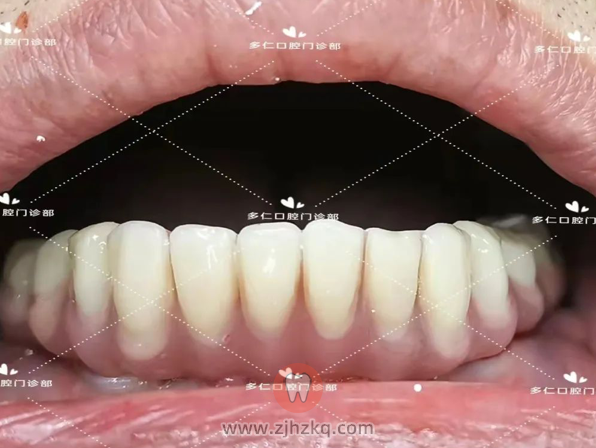

当天种牙,当天得牙。做完即刻修复的大哥非常满意,打算修复好下颌后,再来进行上颌种植手术。

4个月后,换下即刻修复义齿,戴上最终修复义齿后,大哥说:“本来我就爱打扮,牙齿弄好后,面貌都改善好多,好看。”当场大哥就预约好了上颌种植时间。